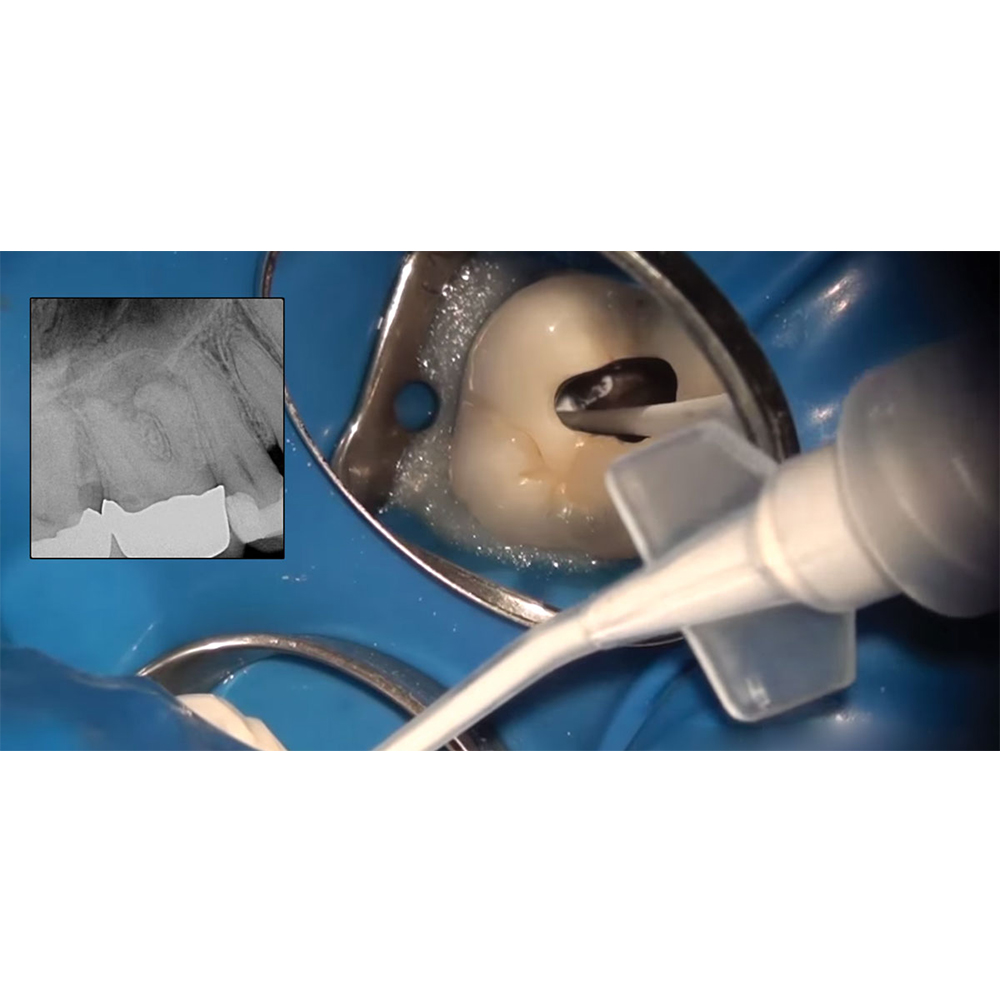

Calcium Silicate-based Bio-ceramic Root Canal Sealer